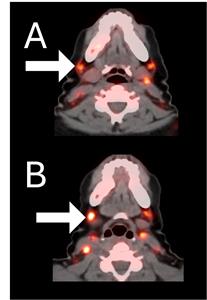

Before BriaCell Treatment Image A: CD8 ImmunoPET image

Pre-treatment imaging of cervical (neck) lymph nodes with moderate uptake indicating presence of some CD8+ cytotoxic (“killer”) T cells.

After BriaCell Treatment Image B: CD8 ImmunoPET image

Post treatment enhancement of cervical (neck) lymph nodes indicating immune system activation and increased presence of CD8+ cytotoxic T cells.

Example 2 Images (Patient 15-005): CD8 ImmunoPET images pre (A) and post (B) Bria-IMT treatment

Example 2 Images (Patient 15-005)

CD8 ImmunoPET images pre (A) and post (B) Bria-IMT treatment